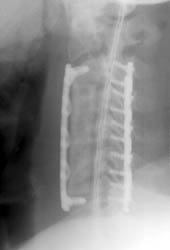

Lateral radiograph taken immediately after the initial operation. The

C4, C5, C6 corpectomies with central strut graft placement is seen, and an

anterior fixation plate with screws at the C3 and T1 levels are identified. No

immediate hardware complications noted. |